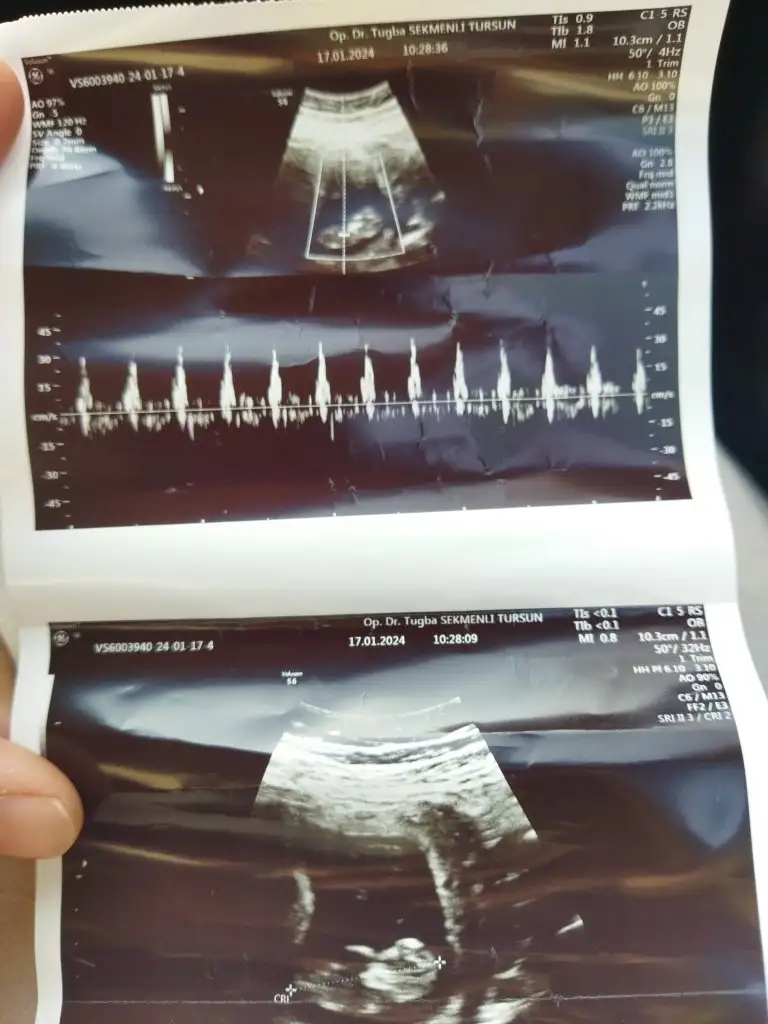

Yaz cnm merak ettimTeşekkür ederiimmAy çok kıpırdaktı zar zor ense kalınlığı ölçüldü zaten

sırt üstü denk getirmek için baya bekletti bizi

ben de erkek hissediyorum ama bakalıımm randevuya 2 buçuk hafta var gösterirse yazıcam buraya